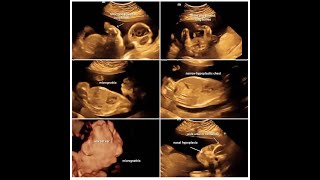

Sonographic Signs Of Campomelic Dysplasia

871

1:39